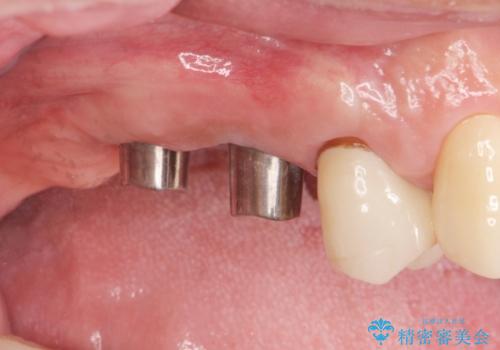

- 歯が抜けてしまい、噛めなくなった右側奥歯の治療を希望され来院されました。

しっかりと咬合機能の回復をするためにインプラント治療を選択されました。

より清掃性の高い、チタン製カスタムアバットメント、審美製・強度に優れるジルコニアインプラントを用いたインプラント治療を計画します。